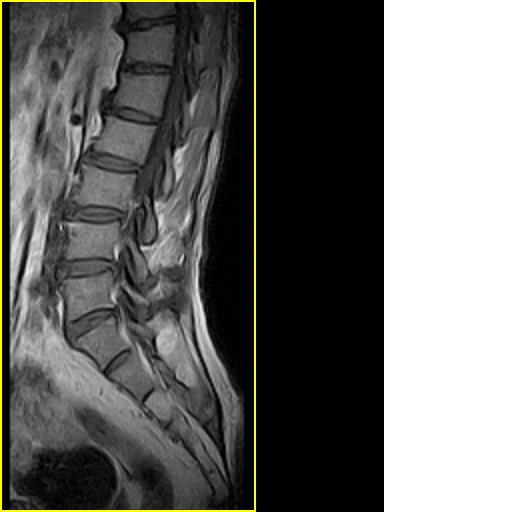

标题: MRI0859:[原创]腰椎,男,78岁,右下肢跛行两月 [打印本页]

男,78岁,右下肢跛行两月.

右侧黄韧带肥厚或钙化,压迫马尾神经所致。必要时行ct扫描。

腰间盘膨出、黄韧带肥厚、可疑先天性腰椎管狭窄。

退行性骨关节病:增生、椎间盘变性、膨出...

退行性病变:增生、椎间盘变性、膨出[l4-5、l5-s1 椎间盘膨出]

我认为这一层面椎间盘应该合并左外侧型突出。

退行性骨关节病:增生、椎间盘变性、膨出..黄韧带肥厚.